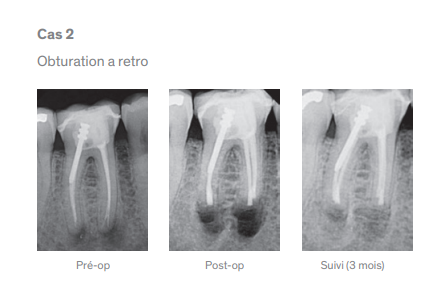

“Le durcissement de TotalFill BC RRM Fast Set Putty accéléré en présence d’hydratation, améliore l’efficacité du traitement et la résistance à la dissolution. TotalFill BC RRM Fast Set Putty constitue une évolution logique du traitement réparateur et de l’obturation à retro, tout autant qu’il démontre les avantages des biocéramiques prémélangées.”